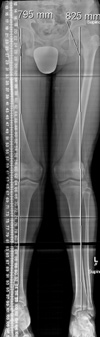

Scanogram of a 13-year-old boy. The measurements at top indicate that his right leg is 30 mm (3 cm) shorter than his left leg.

Reproduced from Song K (ed): Orthopaedic Knowledge Update Pediatrics 4. Rosemont, IL. American Academy of Orthopaedic Surgeons, 2011, p. 225.